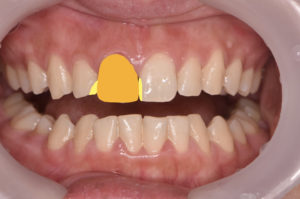

術中

黄色:ダイレクトボンディング

オレンジ:ジルコニアセラミッククラウン

また、模型上で事前にシミュレーションをすることで、ダイレクトボンディングにより欠けた部分の形態の再現が精度良くでき、審美的にも満足の行く治療となりました。

また、欠けた部分の治療としてはラミネートベニアやセラミッククラウンなどの治療法があります。しかし歯を削る事を考え、このケースではダイレクトボンディングにより修復したため無切削による治療ができたのではないかと考えられます。